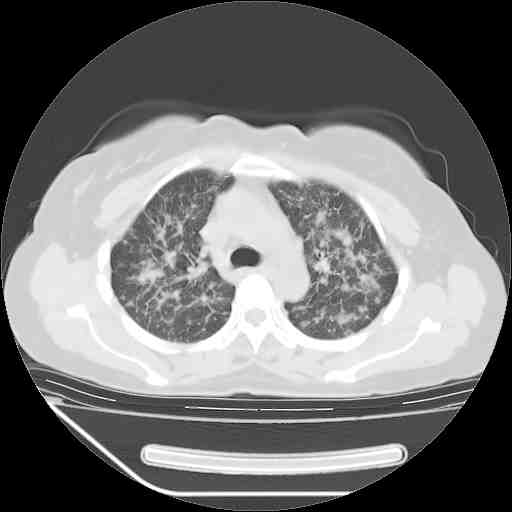

考虑  腺癌肺内转移,治疗较前病灶缩小、减少

支持肺癌并肺内淋巴管转移,

肺癌并肺内转移,这种疾病治疗后在影像上看略有好转,不是很显著,但是肿瘤治疗效果影像只是一方面。

支持肺癌并肺内淋巴管炎,  原发灶小了,但转移较前片明显了.

支气管血管束粗而乱,考虑肺癌肺内淋巴管转移,右侧乳房第一二层软组织成份较左侧多,不会有问题吧?

支持右肺下叶周围型肺癌并肺内淋巴管炎,  原发灶小了,但转移较前片明显了.。

标准的细支气管肺泡癌呀!治疗后病情有所控制,也没治愈的迹象!